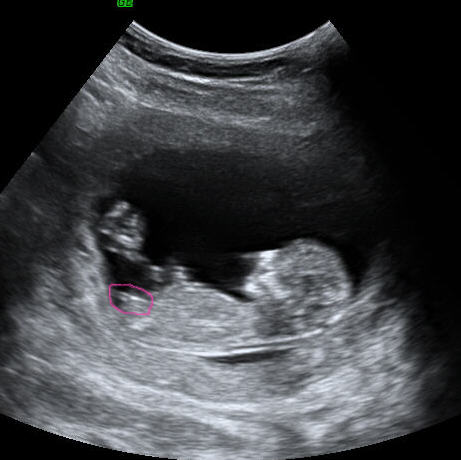

I am convinced that every 12 week u/s I see of a girl shows her head at the left side of the pic. My 12 wk shows the head on the right which I am convinced means its a boy (based on ramzi theory) and I am desperately seeking hope that I could be wrong about this..Thanks!